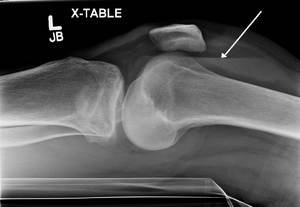

| Lipohemarthrosis (blood and fat in the joint space) seen in a person with a subtle tibial plateau fracture. The arrow indicates a fluid level between the upper fat component and the lower blood component. | |